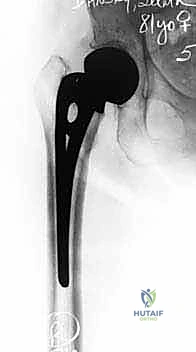

2. من حيث طريقة التثبيت في العظم (أسمنتي مقابل غير أسمنتي)

| نوع التثبيت | المفصل الأسمنتي (Cemented) | المفصل غير الأسمنتي (Uncemented) |

|---|---|---|

| طريقة التثبيت | يتم استخدام مادة "الأسمنت العظمي" (Bone Cement - PMMA) لتثبيت الساق المعدنية بقوة داخل تجويف عظم الفخذ. | يتم إدخال الساق المعدنية (المغطاة بمادة خشنة) بالضغط (Press-fit)، وينمو العظم الطبيعي لاحقاً ليمسك بها. |

| لمن يُستخدم؟ | المرضى كبار السن، ولمن يعانون من هشاشة عظام شديدة أو اتساع في القناة العظمية. | المرضى الأصغر سناً (نسبياً)، أو من يمتلكون جودة عظام ممتازة وقوية. |

| الميزة الرئيسية | تثبيت فوري وقوي جداً، يسمح للمريض بتحميل وزنه كاملاً والمشي في اليوم التالي مباشرة. | يتجنب المخاطر النادرة المرتبطة بالأسمنت العظمي، ويوفر اندماجاً بيولوجياً مع العظم. |